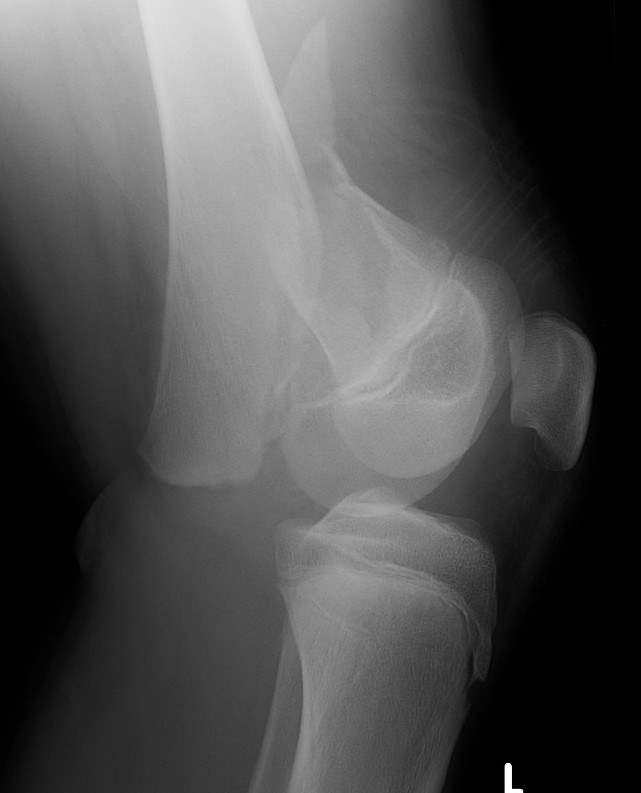

Distal Femoral Fracture SH2 APDistal Femoral Fracture SH2 Lateral

Salter Harris Type II